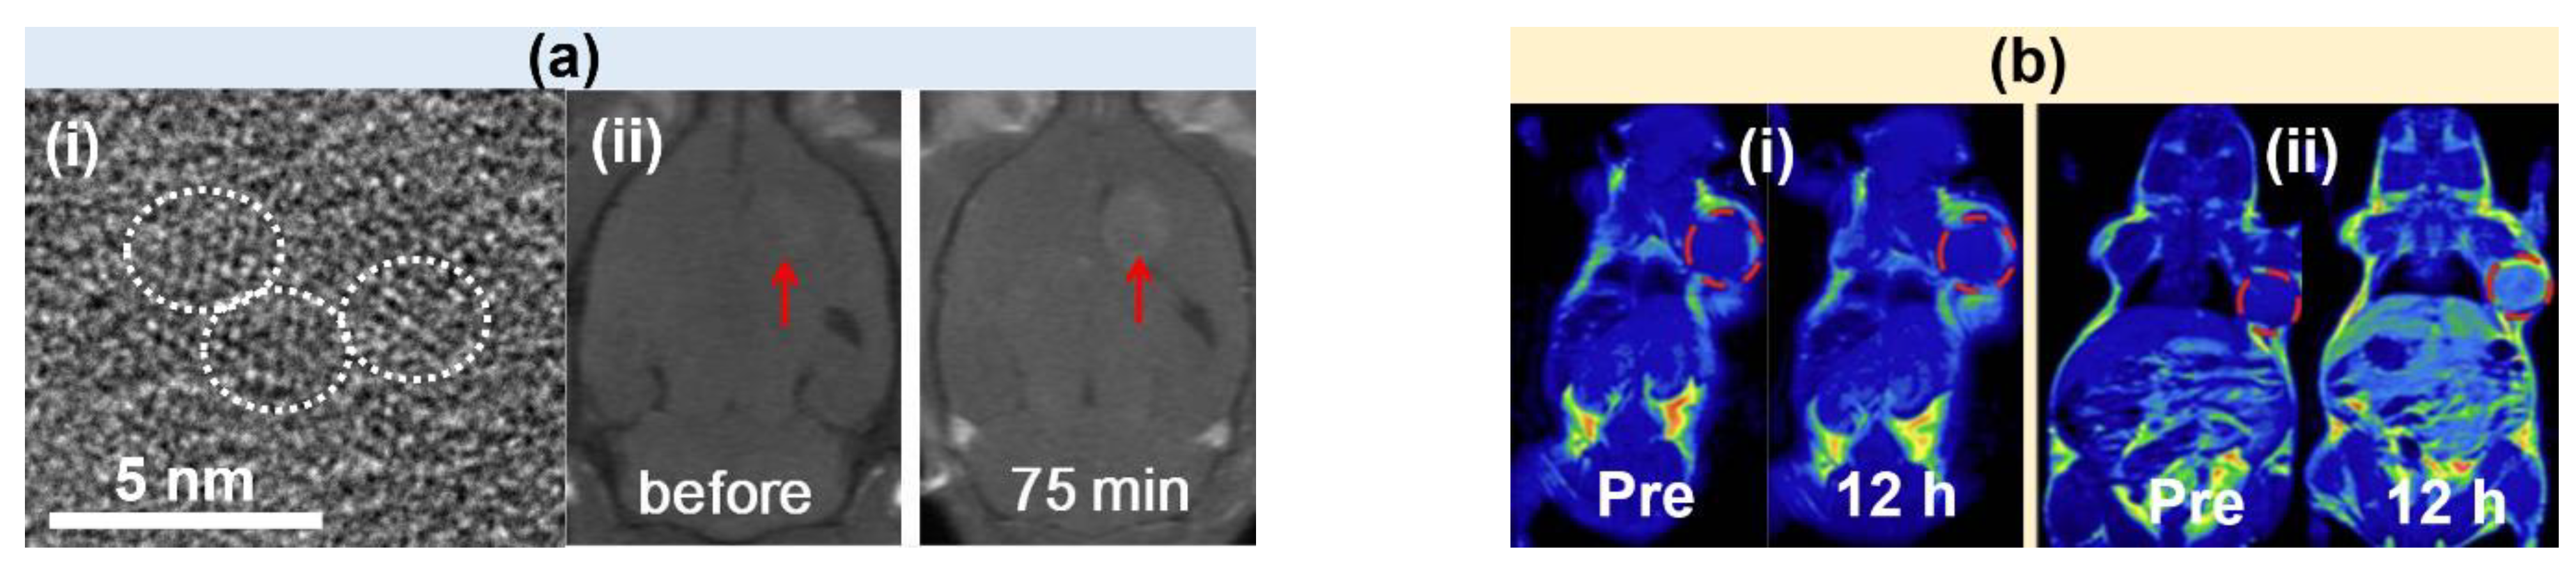

- Wei, R.; Liu, K.; Zhang, K.; Fan, Y.; Lin, H.; Gao, J. Zwitterion-Coated Ultrasmall MnO Nanoparticles Enable Highly Sensitive T1-Weighted Contrast-Enhanced Brain Imaging. ACS Appl. Mater. Interfaces 2022, 14, 3784–3791. [Google Scholar] [CrossRef]

- Xiao, J.; Tian, X.M.; Yang, C.; Liu, P.; Luo, N.Q.; Liang, Y.; Li, H.B.; Chen, D.H.; Wang, C.X.; Li, L.; et al. Ultrahigh relaxivity and safe probes of manganese oxide nanoparticles for in vivo imaging. Sci. Rep. 2013, 3, 3424. [Google Scholar] [CrossRef]

- Mekuria, S.L.; Debele, T.A.; Tsai, H.-C. Encapsulation of Gadolinium Oxide Nanoparticle (Gd2O3) Contrasting Agents in PAMAM Dendrimer Templates for Enhanced Magnetic Resonance Imaging in Vivo. ACS Appl. Mater. Interfaces 2017, 9, 6782–6795. [Google Scholar] [CrossRef]

- Marasini, S.; Yue, H.; Ghazanfari, A.; Ho, S.L.; Park, J.A.; Kim, S.; Cha, H.; Liu, S.; Tegafaw, T.; Ahmad, M.Y.; et al. Polyaspartic Acid-Coated Paramagnetic Gadolinium Oxide Nanoparticles as a Dual-Modal T1 and T2 Magnetic Resonance Imaging Contrast Agent. Appl. Sci. 2021, 11, 8222. [Google Scholar] [CrossRef]